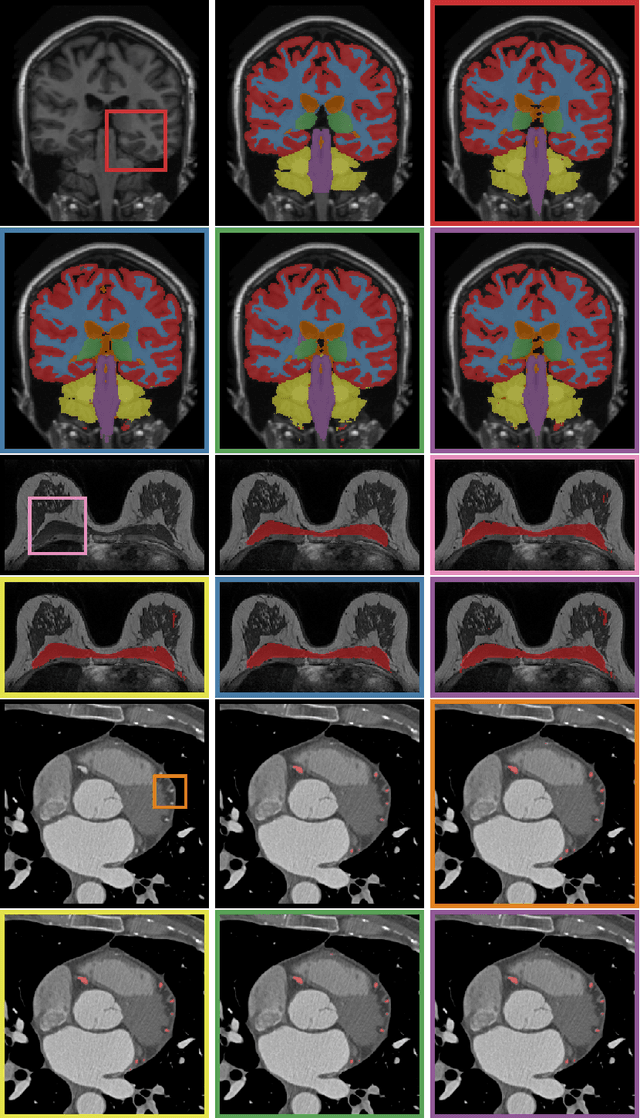

Abstract:Automatic segmentation of medical images is an important task for many clinical applications. In practice, a wide range of anatomical structures are visualised using different imaging modalities. In this paper, we investigate whether a single convolutional neural network (CNN) can be trained to perform different segmentation tasks. A single CNN is trained to segment six tissues in MR brain images, the pectoral muscle in MR breast images, and the coronary arteries in cardiac CTA. The CNN therefore learns to identify the imaging modality, the visualised anatomical structures, and the tissue classes. For each of the three tasks (brain MRI, breast MRI and cardiac CTA), this combined training procedure resulted in a segmentation performance equivalent to that of a CNN trained specifically for that task, demonstrating the high capacity of CNN architectures. Hence, a single system could be used in clinical practice to automatically perform diverse segmentation tasks without task-specific training.